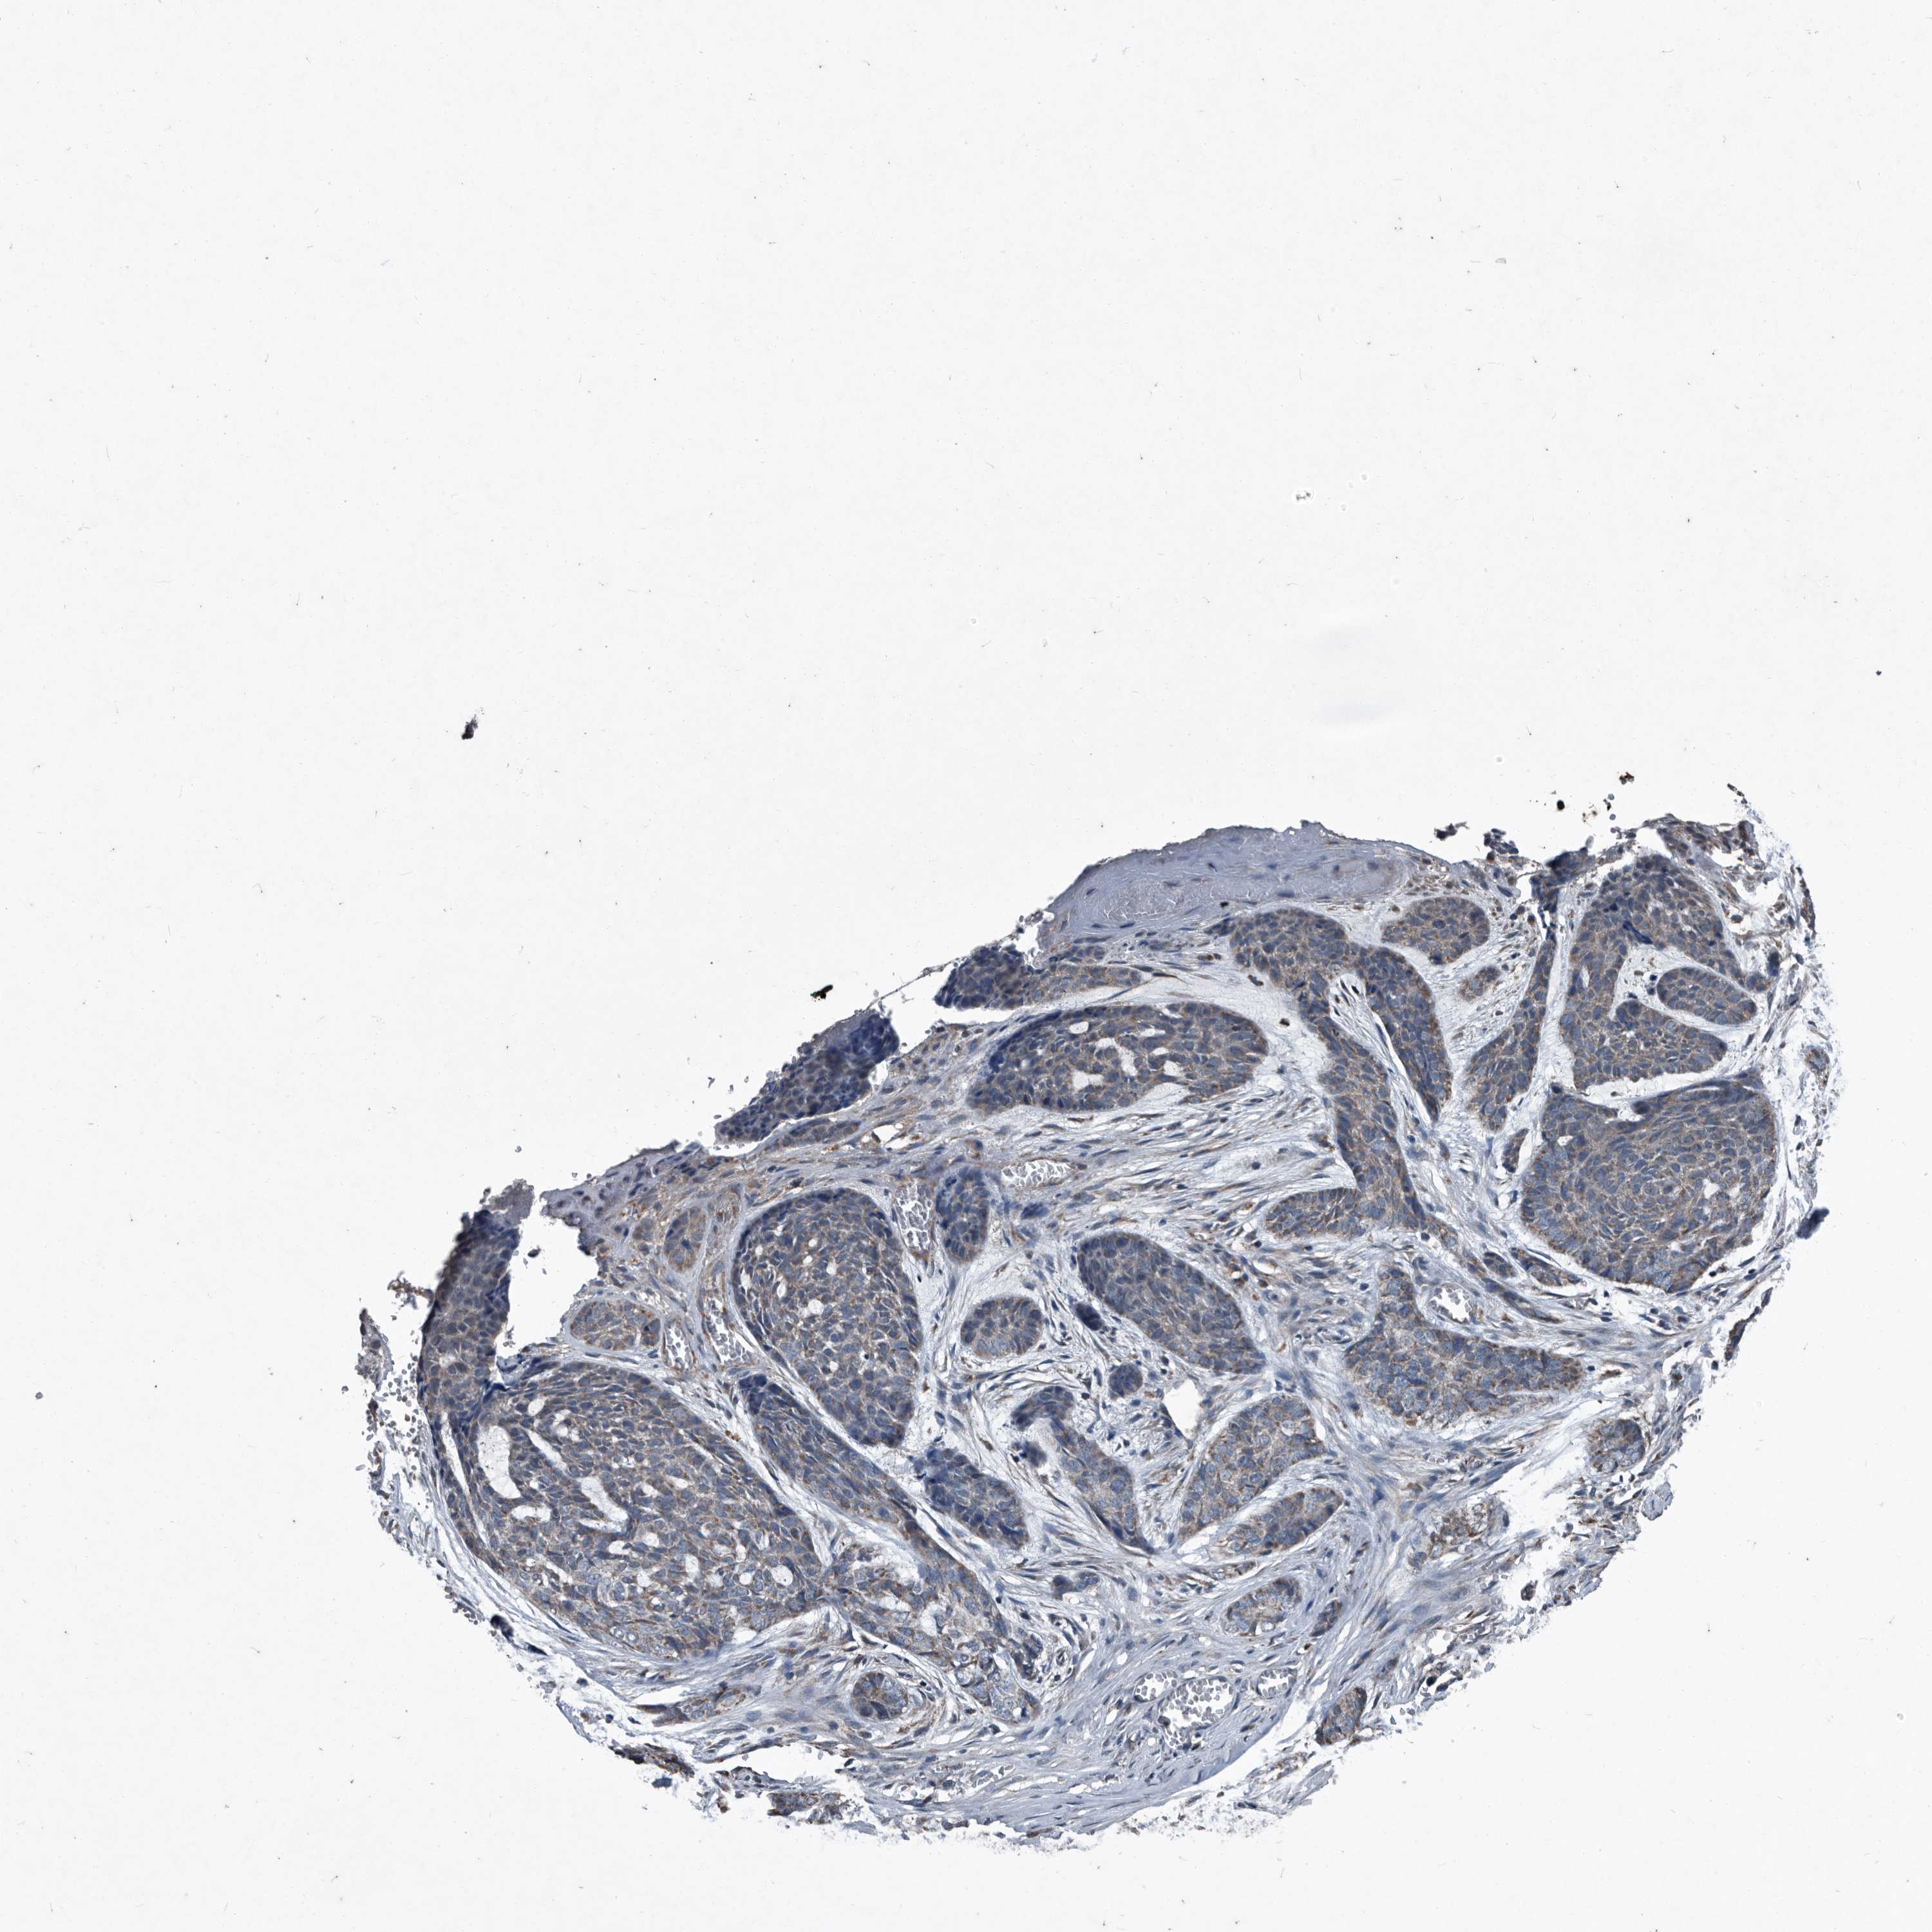

SKIN CANCER - Protein expressioni

A mouse-over function shows sample information and annotation data. Click on an image to view it in a full screen mode. Samples can be filtered based on level of antibody staining by selecting one or several of the following categories: high, medium, low and not detected. The assay and annotation is described here.

Antibody stainingi

Antibody staining in the annotated cell types in the current human tissue is reported as not detected, low, medium, or high, based on conventional immunohistochemistry profiling in selected tissues. This score is based on the combination of the staining intensity and fraction of stained cells.

Each image is clickable and will lead to virtual microscopy that enables deeper exploration of all samples and also displays staining intensity scores, fraction scores and subcellular localization as well as patient and tissue information for each sample.

Antibody HPA045174

Antibody CAB032821

Staining

High

Medium

Low

Not detected

Intensity

Strong

Moderate

Weak

Negative

Quantity

>75%

75%-25%

<25%

None

Location

Nuclear

Cytoplasmic/membranous

Cytoplasmic/membranous,nuclear

Basal cell carcinoma

BCC, high aggressive

Squamous cell carcinoma, NOS

Squamous cell carcinoma, metastatic, NOS